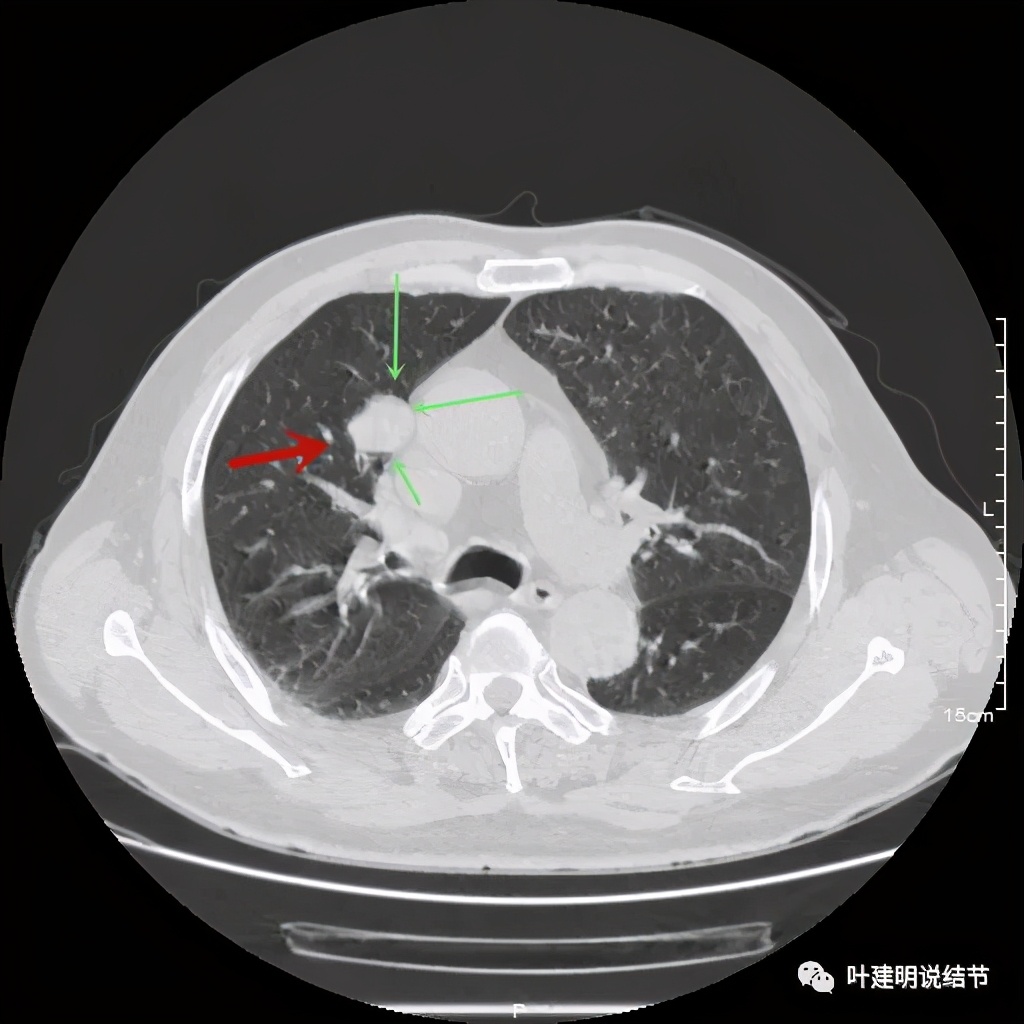

上图示病灶局部点状高密度(蓝色);边缘过于光滑(绿色)

上图示病灶密度不均,但边缘过于光滑(绿色);支气管似有截断(粉色);局部有点状钙化(蓝色)

上图也示病灶密度不均,但边缘过于光滑(绿色);支气管似有截断(粉色);局部有点状钙化(蓝色)